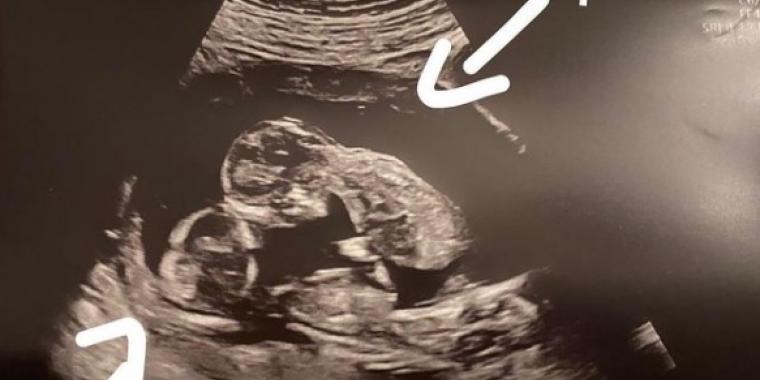

Da Gina Dewdney under hendes graviditet skulle til ultralydsscanning, opdagede lægerne at hun ventede ikke bare et eller to, men hele tre børn.

“Jeg blev så chokeret, da jeg pludselig så 3 hoveder på skærmen”.

Da Gina efter 31 ugers graviditet skulle føde, opdagede lægerne imidlertid noget helt usædvanligt ved den ene baby.

1 ud af 200.000.000

Jaxon, som drengen kaldes, forblev inde i den intakte moderkage. At der bliver en trilling tilbage i den er så usædvanligt, at det hører til 1 ud af 200.000.000.

Moderkagen er det, der omgiver og beskytter barnet, som en pose væske, der ligner en boble. At en af Ginas tre babyer forblev i denne gennem fødslen var enestående.